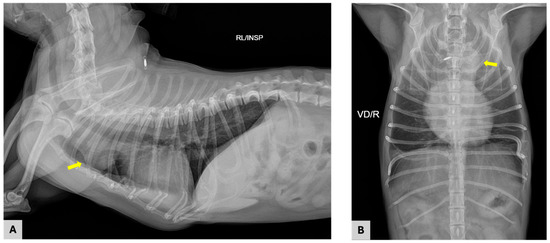

A 10-year-old castrated male Chihuahua weighing 3.06 kg was presented with a chronic, progressively worsening cough of five months’ duration. Diagnostic imaging, including thoracic radiography and computed tomography, identified a well-defined cranial mediastinal mass consistent with a thymic tumor. Surgical excision was performed via median sternotomy with complete thymectomy. Following tumor removal, sternal closure was achieved using a non-absorbable ultra-high-molecular-weight polyethylene (UHMWPE) suture material (FiberWire®, Arthrex, Naples, FL, USA). Histopathological examination confirmed the diagnosis of an epithelial-predominant thymoma with narrow but complete surgical margins. Postoperative recovery was uneventful, and the dog was discharged three days after surgery. Clinical signs, including coughing, progressively improved during follow-up. Radiographic evaluation performed up to postoperative day 57 demonstrated stable sternal alignment without evidence of dehiscence, implant-related complications, or disease recurrence. This report describes the first clinical case of FiberWire use for median sternotomy closure following thymectomy in a dog. The favorable clinical and radiographic outcomes observed during postoperative follow-up suggest that FiberWire may represent a viable alternative to traditional stainless-steel wire for sternal fixation in canine thoracic surgery. Full article

Figure 1